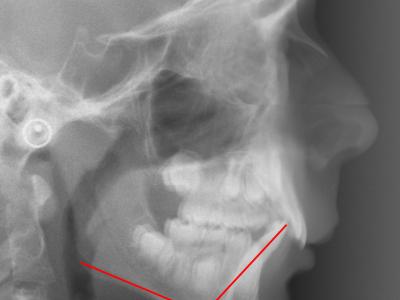

Téléradiographie de profil initiale, IMPA = 108° (a),

à 11 mois post-opératoires avec 8 mois de nivellement sur arc rond, les incisives mandibulaires se redressent spontanément de 11° (IMPA = 97°) et la concavité de la symphyse diminue significativement (b),

superposition avec le logiciel Procuste (Rouge = Avant / Bleu = Après) (c).